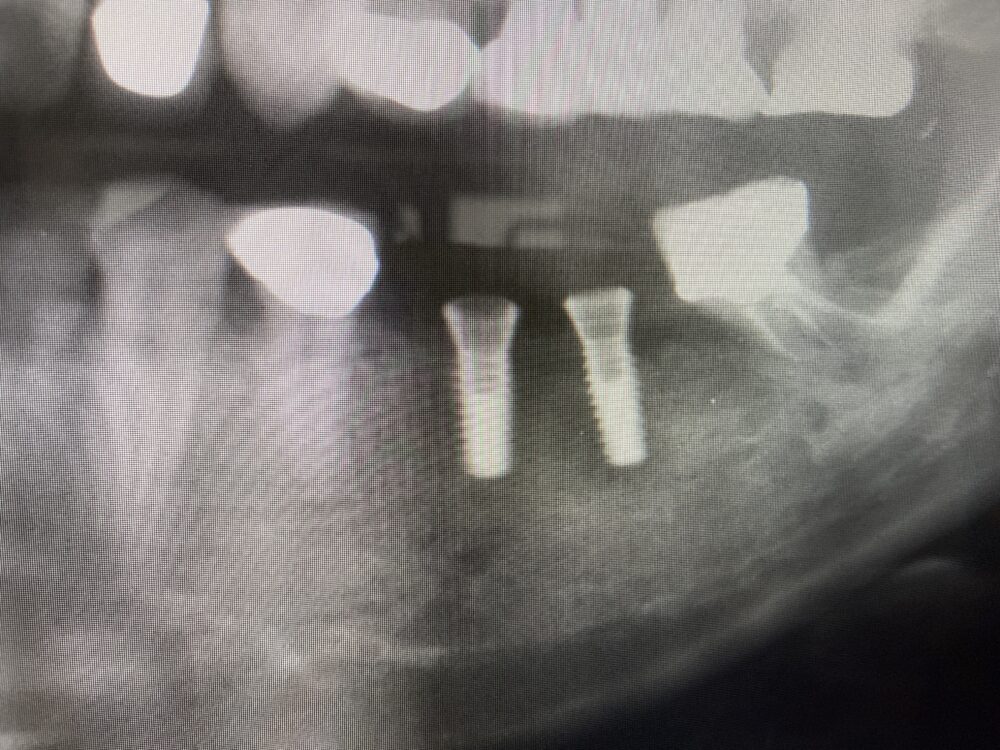

まずは症例1

左下奥歯に義歯がありました。

患者さんの要望により、インプラント治療を始めました。

インプラント治療は、CT撮影から始まります。

CT画像を3次元的に分析し、太い神経を避けてチタンのネジを埋め込みます。

ネジが骨と一体化するまで3ヶ月間待ちます。

その間、第2大臼歯の骨が少し吸収してきました。